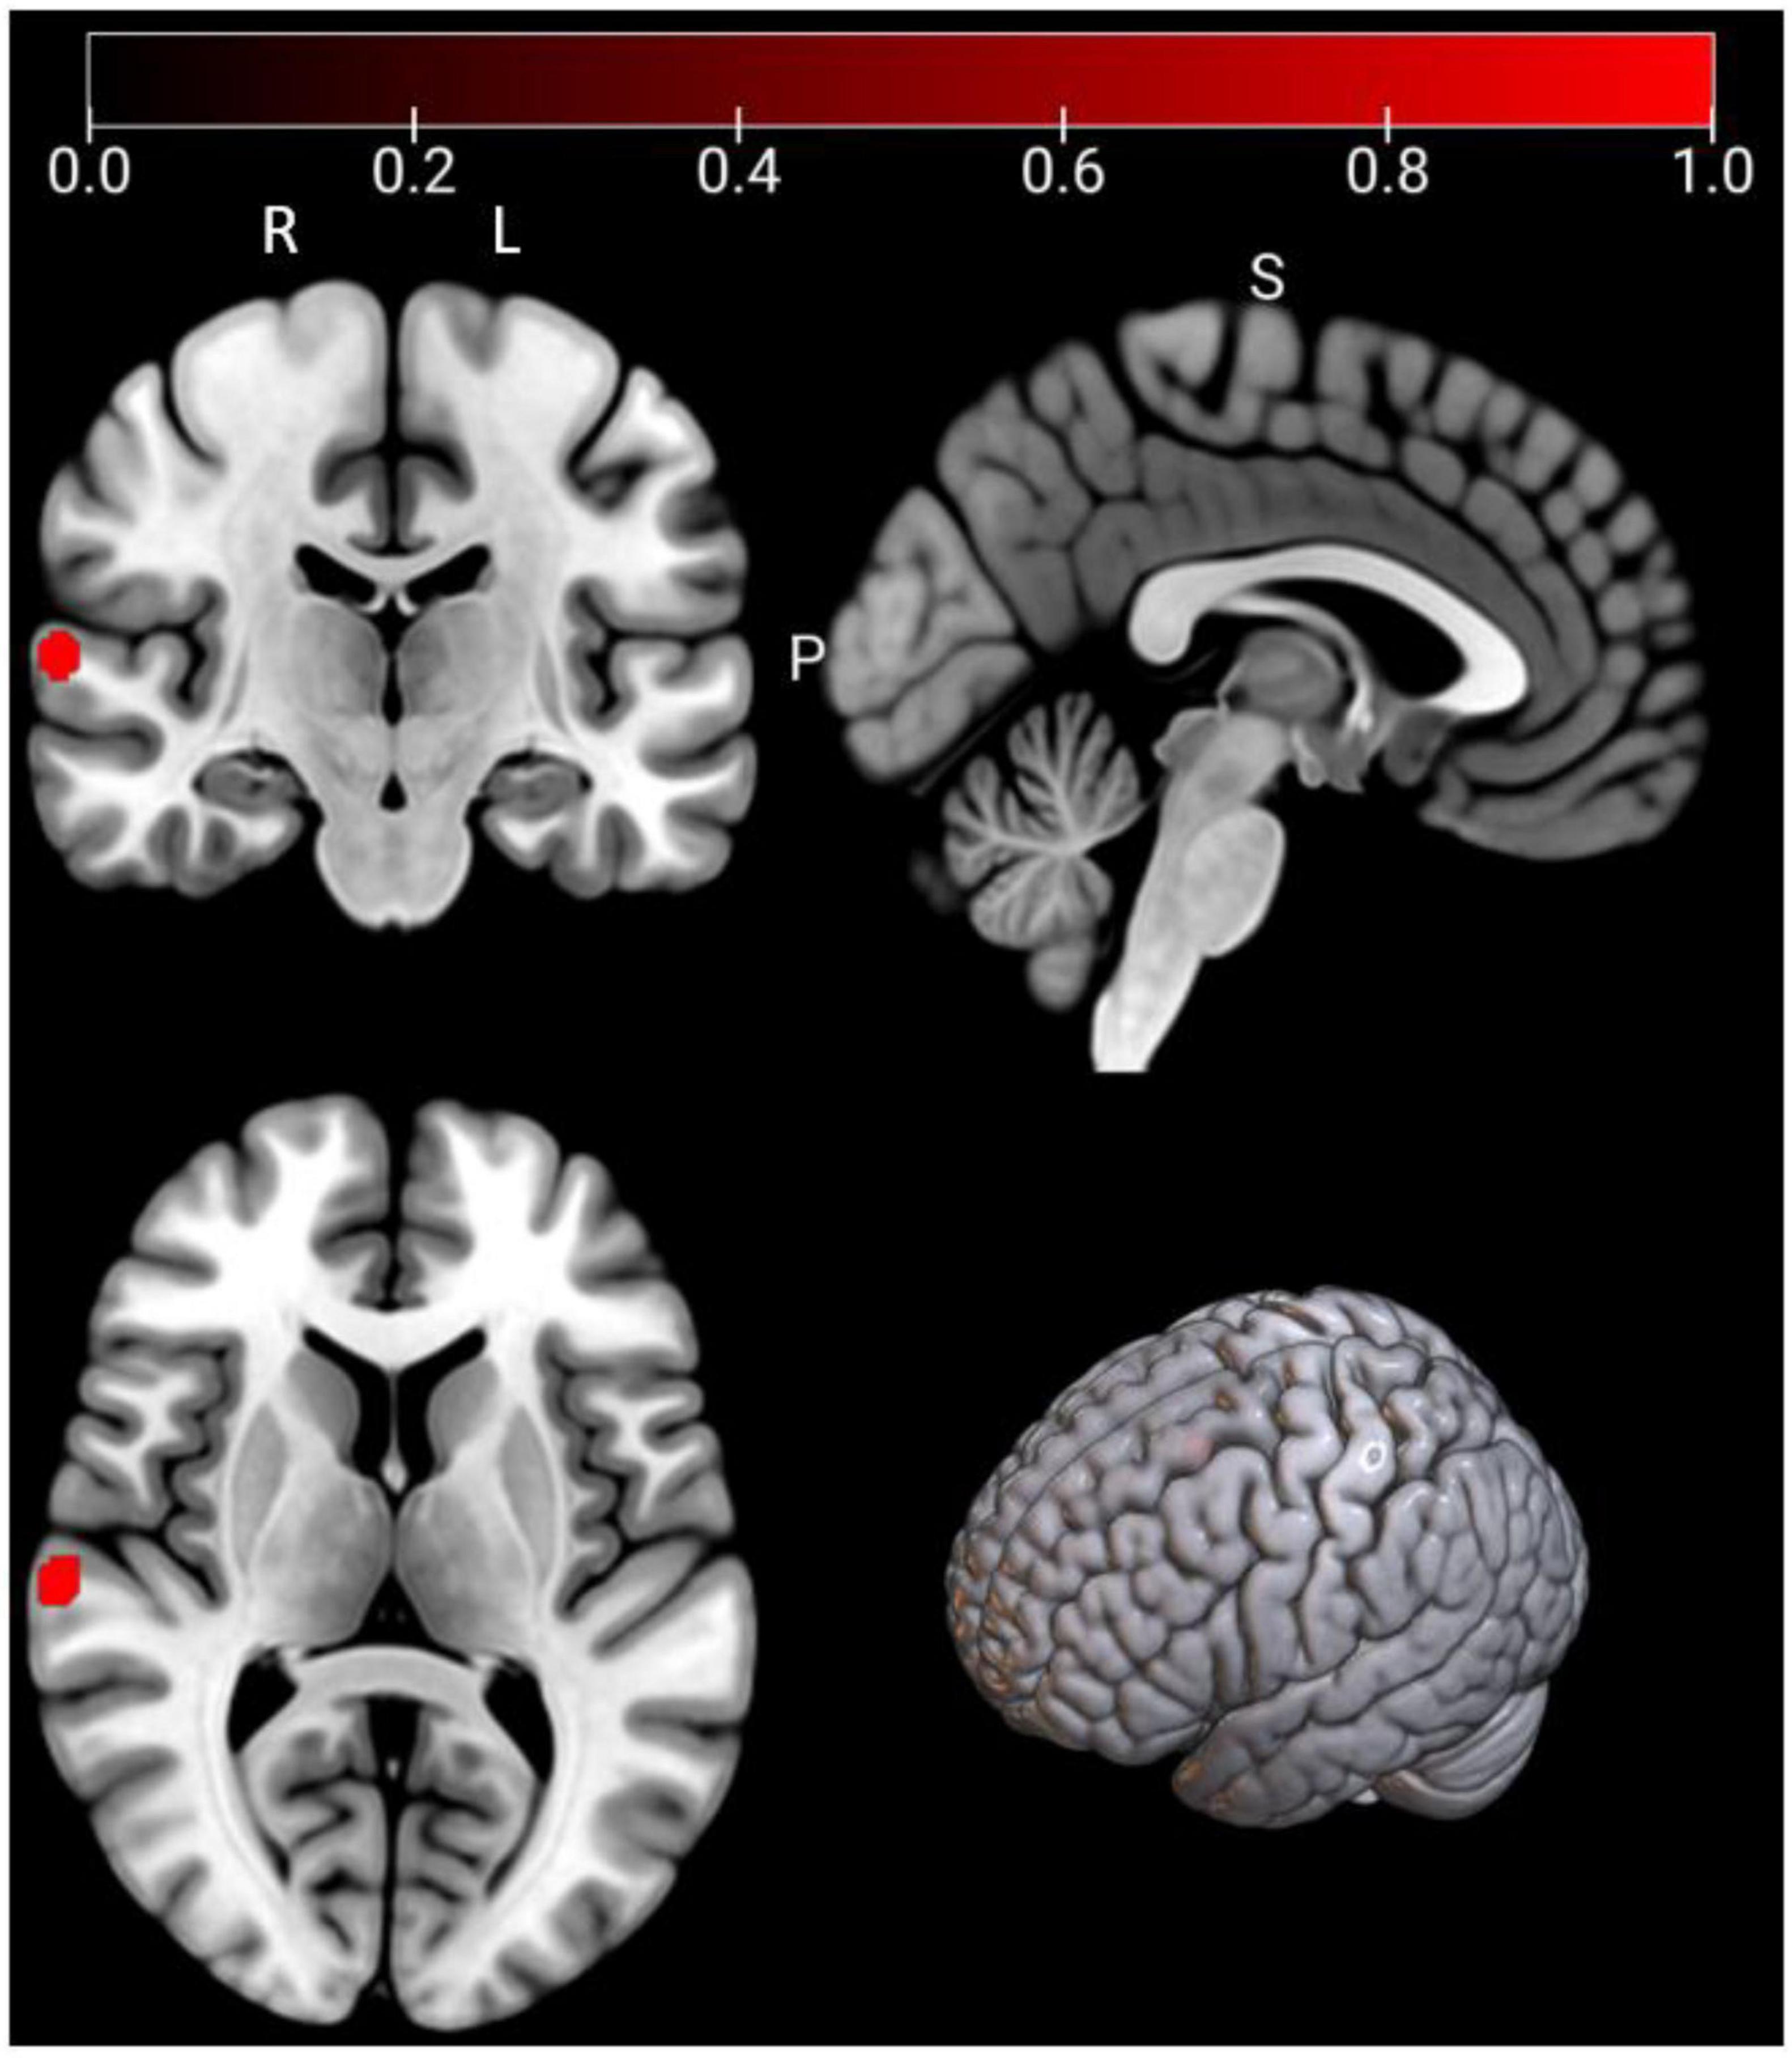

As shown in Figure 3 and Table 3, according to the ALE result, a significant cluster of task-based fMRI studies was observed in the left pallidum in this ALE meta-analysis. Jackknife analyses have also further validated these findings, indicating the robustness and high replicability in the observed cluster: left pallidum (15 out of 16 replicabilities). See Supplementary Table 3 for more details.

FIGURE 3

Four brain scans showing different views with areas highlighted in red, indicating specific regions of interest. The top row displays coronal and sagittal views, while the bottom row shows an axial view and a 3D brain model. A color scale from zero to one is shown above, emphasizing intensity variations in red.

Figure 3. Emotional well-being (EWB) meta-maps (marked with red) of task-based functional magnetic resonance imaging (fMRI) studies (the task-dependent modality). “L” refers to the left hemisphere, and “R” refers to the right hemisphere.